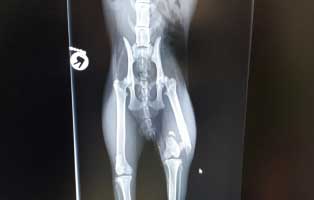

Fundkater mit Beinbruch braucht dringend Op

Dieser Kater wurde auf einer Futterstelle gefunden. Vor Schmerzen konnte er nicht laufen und wir wurden um Hilfe gebeten. Wir holten den armen halbwilden Kater ab und brachten ihn zum Tierarzt.

Katzenbaby aus Thüringen braucht eine Bein OP

Am 27.11.19 wurden wir von Tierlieben Menschen angerufen, die einen kleinen ca 6 Wochen alten Kater gefunden haben der ängstlich unter einem Auto saß und nicht mehr laufen konnte.